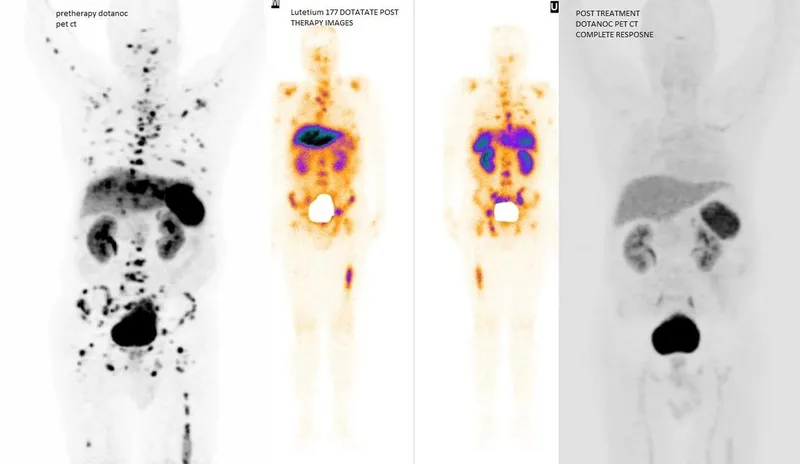

- $^{177}$Lu-DOTATATE

⭐ Peptide Receptor Radionuclide Therapy (PRRT) with $^{177}$Lu-DOTATATE is indicated for unresectable or metastatic, progressive, well-differentiated, somatostatin receptor-positive gastroenteropancreatic neuroendocrine tumors (GEP-NETs).